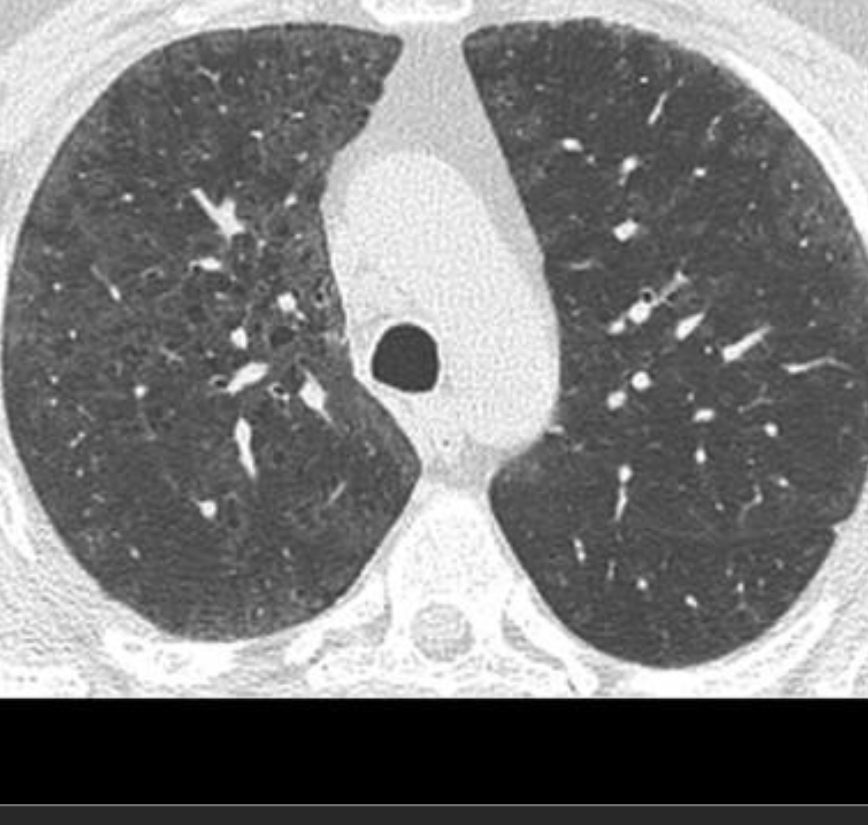

Upper lobe predominant centrilobular ground glass, OR prominent mosaic pattern

Hypersensitivity Pneumonitis

(subacute)

chronic peribronchiolar inflammation w/poorly defined granulomas and giant cells in the interstitium or alveoli on pathology.

lobular GGO

Need constellation of findings to dx: exposure to an offending antigen, characteristic signs and symptoms, abnormal chest findings on physical examination, and abnormalities on pulmonary function tests and imaging